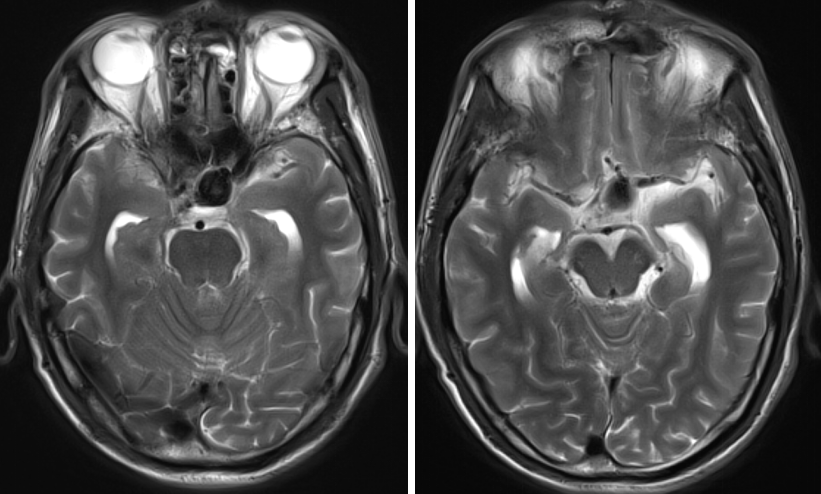

头颅MRI

科内讨论后认为:患者颈内动脉床突旁大动脉瘤诊断明确,患者动脉瘤破裂出血,需急诊手术治疗。术中应先在颈部暴露颈内动脉。采用Dolenc入路硬膜外磨除前床突及视神经管。术中注意保护好眼动脉。暴露动脉瘤后可孤立动脉瘤,并在颈部穿刺颈动脉并逆向抽吸,降低动脉瘤的张力后塑形夹闭动脉瘤。

患者术后病情稳定,神清,语明,双侧瞳孔等大等圆,直径约2.5mm,光反应灵敏,视力及视野正常,四肢肌力、肌张力正常。